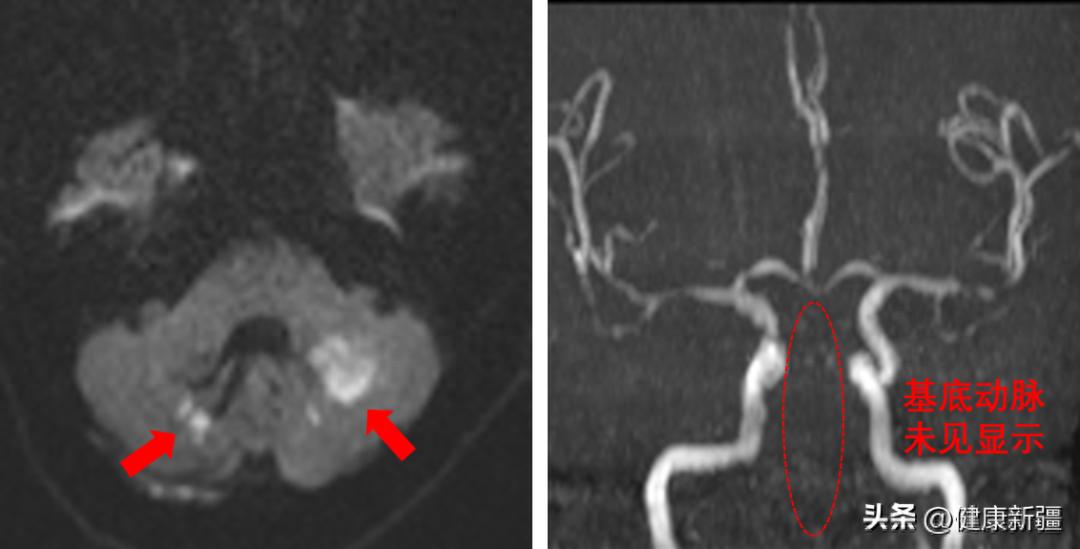

该患者78岁,既往有高血压病史。近日,该患者晨起后突发头晕伴呕吐不适,休息后不适症状不仅未得到缓解,反而逐渐进展加重至四肢瘫痪伴意识丧失,家人随即将患者送至喀什二院急诊。喀什二院神经内科卒中团队快速反应,完善磁共振检查,结果显示颅内多发性急性脑梗死,同时基底动脉未见显影,提示患者为急性基底动脉闭塞引起的脑梗死。

患者CT影像基底动脉是后循环的重要组成部分,由两侧椎动脉汇合而成,负责脑干、丘脑等重要脑区供血,直接负责心跳、呼吸等基本的生命活动。急性基底动脉闭塞是脑卒中最严重的类型,栓塞或动脉粥样硬化狭窄是两大主要病因。栓塞性基底动脉闭塞往往单纯抽吸就可获得成功再通,与此相反,动脉粥样硬化狭窄导致的急性基底动脉闭塞取栓过程更复杂、更耗时,常需要球扩成型和支架植入等补救治疗。